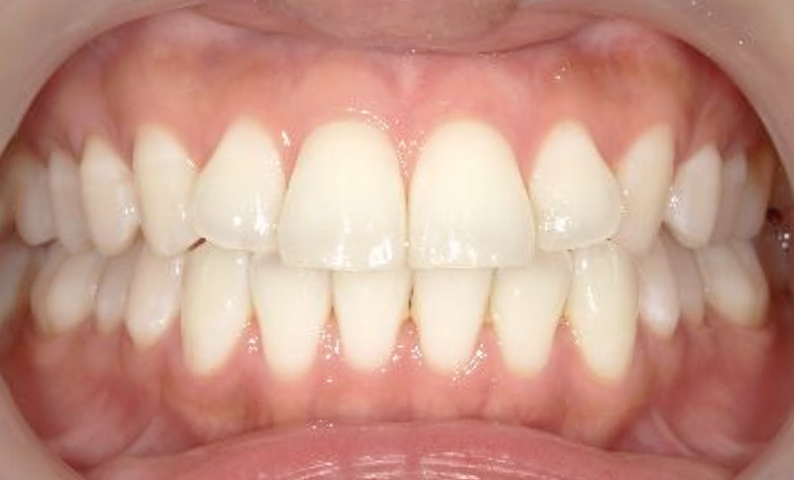

症例_002 前歯「捻転歯」症例

治療期間:10ヶ月金額:54万円+税30代女性少しのねじれ捻転歯前歯の突出感

| Before | After |